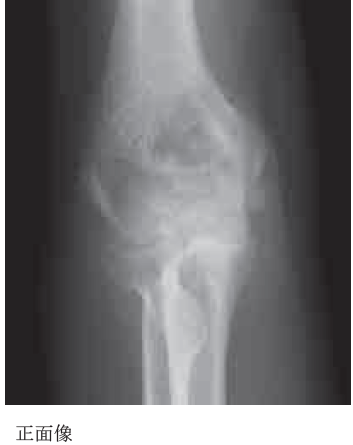

31歳の女性。転倒により右肘を床に強打し、接骨院で施術を受けた。受傷3か月後に肘関節可動域制限を訴え来院した。初診時右肘関節単純X線像を示す。この症例について誤っているのはどれか。2つ選べ。

a. 腱付着部の石灰化である。

b. 早期より病巣切除を行う。

c. エチドロネートは病態を抑制する。

d. 非ステロイド性抗炎症薬は有効である。

e. 血清アルカリホスファターゼ値が上昇する。

正解:a, b

解説:骨化性筋炎

b:骨化が成熟する前(通常6~12か月)に手術を行うと再発リスクが高い

c:骨形成抑制作用のあるビスフォスフォネート(例:エチドロネート)は異所性骨化の予防や進行抑制に使われる。

d:NSAIDs(特にインドメタシン)は、骨芽細胞活性を抑制し、異所性骨化の発生を予防・抑制する効果がある

e:骨形成が活発になる過程で、ALP(骨型)が上昇することがある。特に進行期や成熟期においては明確な所見となる。